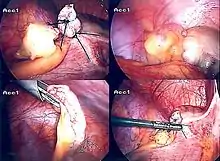

Surgery

The surgical procedure for the removal of the appendix is called an appendectomy. Appendectomy can be performed through open or laparoscopic surgery. Laparoscopic appendectomy has several advantages over open appendectomy as an intervention for acute appendicitis.[73]

Laparoscopic appendectomy

Laparoscopic appendectomy was introduced in 1983 and has become an increasingly prevalent intervention for acute appendicitis.[77] This surgical procedure consists of making three to four incisions in the abdomen, each 0.25 to 0.5 inches (6.4 to 12.7 mm) long. This type of appendectomy is made by inserting a special surgical tool called a laparoscope into one of the incisions. The laparoscope is connected to a monitor outside the person's body, and it is designed to help the surgeon to inspect the infected area in the abdomen. The other two incisions are made for the specific removal of the appendix by using surgical instruments. Laparoscopic surgery requires general anesthesia, and it can last up to two hours. Laparoscopic appendectomy has several advantages over open appendectomy, including a shorter post-operative recovery, less post-operative pain, and lower superficial surgical site infection rate. However, the occurrence of an intra-abdominal abscess is almost three times more prevalent in laparoscopic appendectomy than open appendectomy.[78]